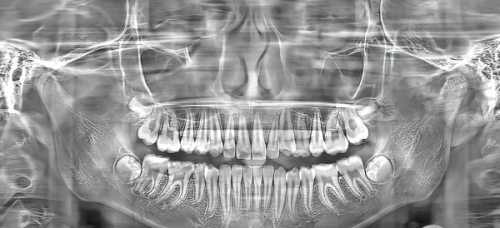

在设备方面,虽然没有详细资料表明其设备的具体情况,但作为一家正规且具有一定规模的连锁口腔诊所,推测其会配备精良的口腔诊疗设备,如口腔CT、数字化牙片机等,这些设备可以帮助医生更正确地诊断病情,为治疗提供有力支持。

在数字化种植方面,临汾侯马雅美口腔诊所在2025年侯马牙科机构中突出了这一优势。数字化种植技术利用精良的计算机辅助设计和制造技术,医生可以在术前通过口腔CT等设备获取患者口腔的详细数据,进行精细的种植方案规划。在手术过程中,医生可以根据数字化导板进行严谨的种植体植入,大大提高了种植的正确性和成功几率,减少了手术创伤和患者的痛苦。